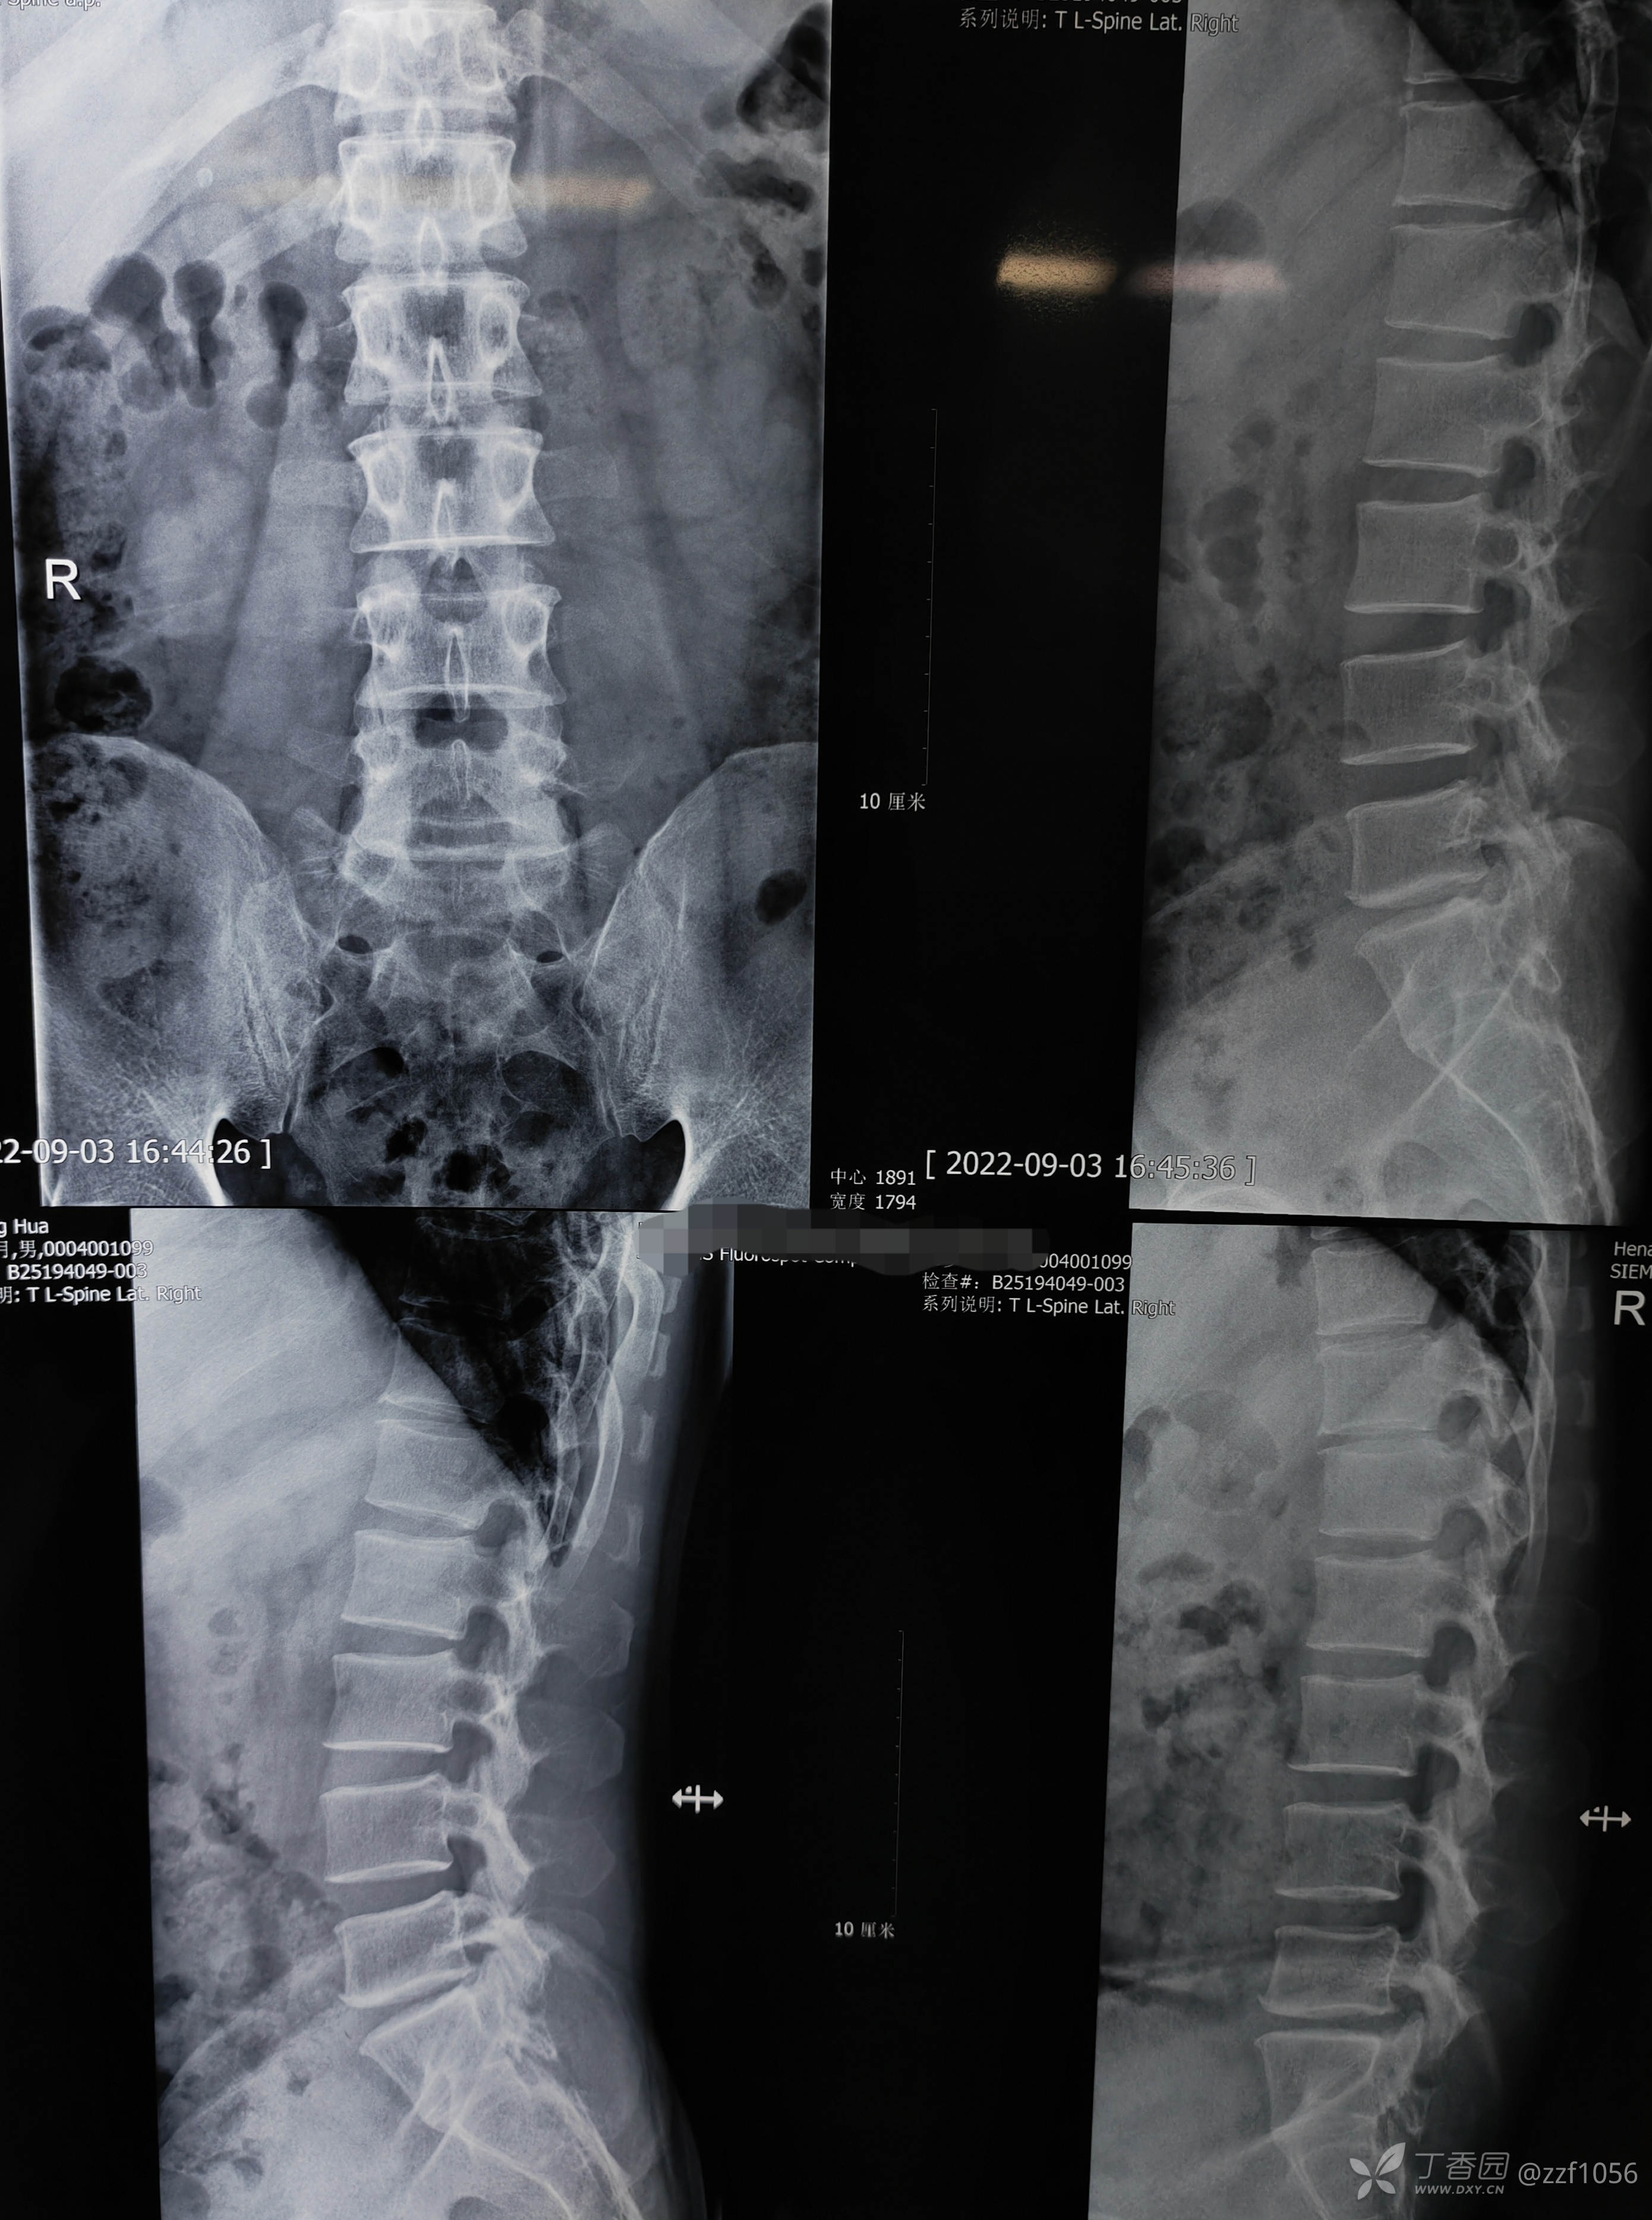

先睹影像

肋骨够数吗?

L1还是T12,三长四短五肥大

脱出明显

左侧,貌似两块